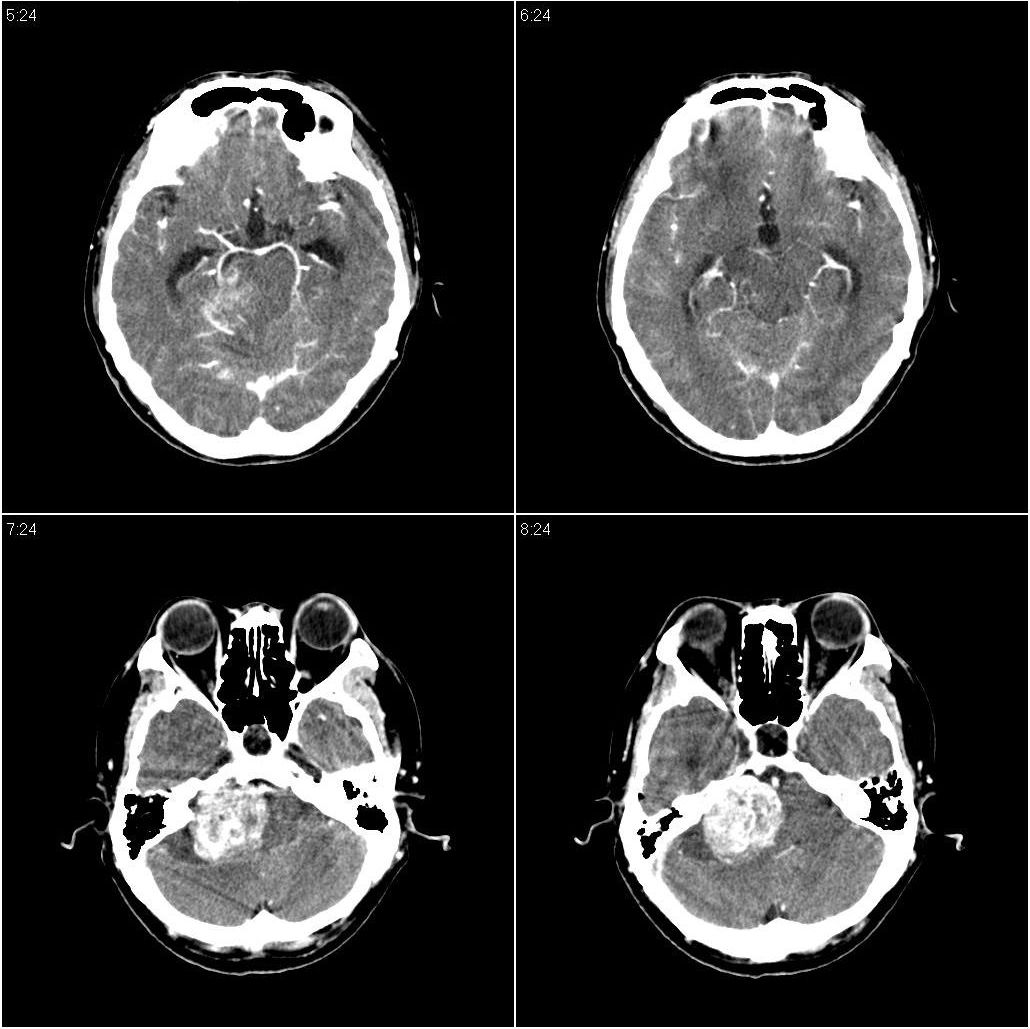

标题: CT16665:男,34岁。近来发现视力不好、眼花。 [打印本页]

标题: CT16665:男,34岁。近来发现视力不好、眼花。

考虑小脑占位性病变,建议ct增强或mri检查。

支持右侧小脑半球占位性病变伴梗阻性脑积水。建议增强,上传骨窗,除外听神经瘤

脑干密度减低,增大,与周围界限不清,四脑室受压显示不清;右侧桥小脑角区似可见稍高密度影;建议行mri检查。

后颅窝占位性病变,建议mri检查!

右侧小脑区稍低不均密度占位病变,边界不甚清楚,四脑室受压。建议ct增强或mri进一步检查。